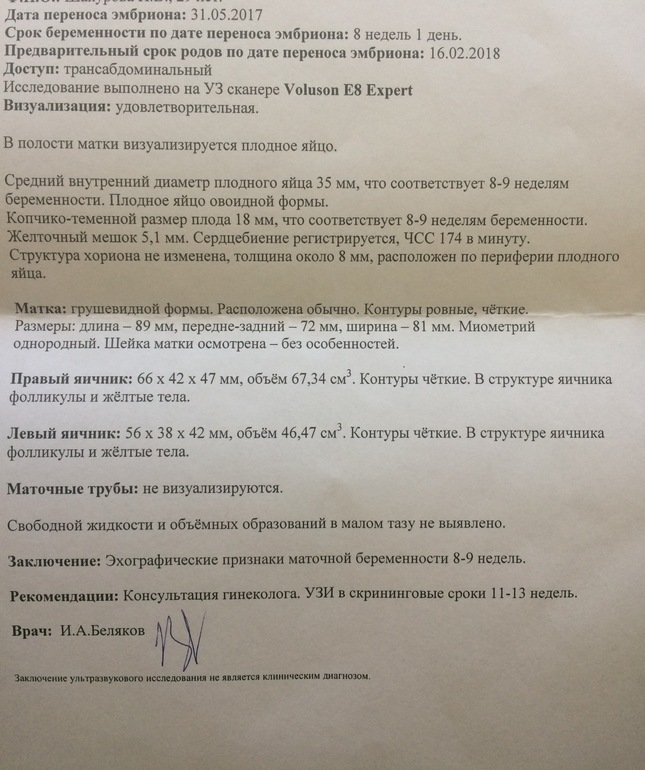

Фотографии на ранних этапах беременности